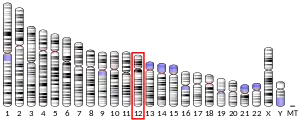

Gene

The human ETV6 gene is located at position "13.2" on the short (i.e. "p") arm of chromosome 12, i.e. its notated position is 12p13.2. The gene has 8 exons and two start codons, one located at exon 1 at the start of the gene and an alternative located upstream of exon 3. ETV6 codes for a full length protein consisting of 452 amino acids; the gene is expressed in virtually all cell types and tissues.[5][6] Mice depleted of the ETV6 gene by Gene knockout die between day 10.5 and 11.5 of embryonic life with defective yolk sac angiogenesis and extensive losses in mesenchymal and neural cells due to apoptosis. Other genetic manipulation studies in mice indicate that the gene is required for the development and maintenance of bone marrow-based blood cell formation and the vascular network.[5][7]